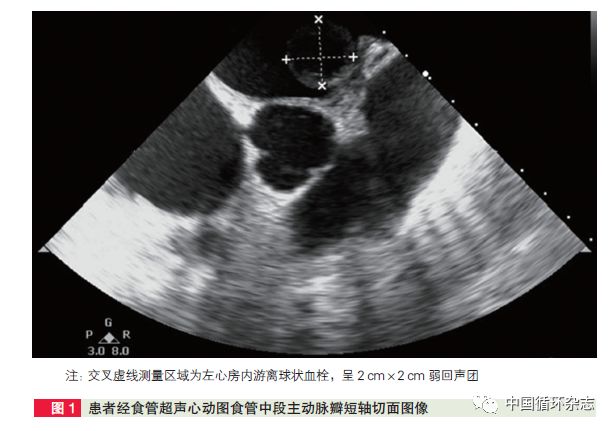

术中经食管超声心动图和心脏切开后均发现,左心房游离球状血栓约2 cm×2 cm。术中发现,右心房及右心室明显增大,中心静脉压力为30 cmH2O;左心耳内含少量血栓,二尖瓣瓣膜增厚,瓣口重度狭窄;三尖瓣瓣膜增厚,前后交界融合,瓣叶挛缩,呈风湿改变。

超声心动图:风湿性二尖瓣重度狭窄,三尖瓣中度反流,左心房附壁血栓, 重度肺动脉高压,左心室舒张末期容积38 ml,射血量22 ml,左心室射血分数58%。